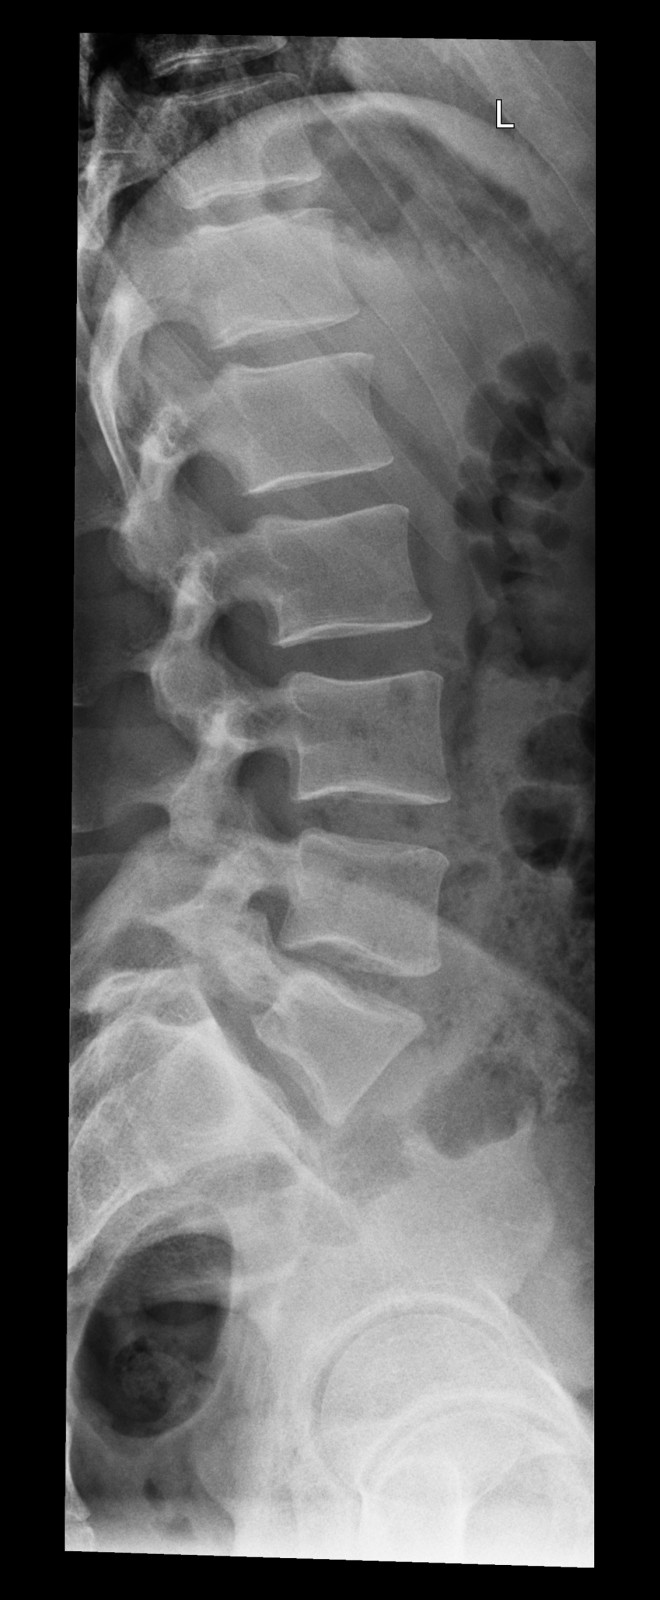

Röntgenfall des Monats Juni 2017 mit Auflösung

34 jähriger Patient mit exazerbierter Lumbago. Beruf: Plattenleger

seitlich

Bild vergrössern